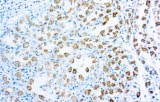

Primary antibodies for immunohistochemistry CE/IVD - Pediatric pathology

Perinatal/paediatric pathology is a medical subspecialty with particular expertise in diseases affecting the placenta, fetus, infant and child. Although many conditions that affect adults also affect children, pediatric pathology includes many conditions found only in patients younger than 18 years of age. One group of conditions involving the infant population is congenital anomalies. A malformation is a congenital anomaly due to an intrinsic defect in development. A disruption occurs when a normally developing organ is secondarily damaged by another process. A sequence is a collection of several anomalies, all of which are due to one malformation, disruption, or deformation. Finally, a syndrome is a group of related anomalies. An other group is the pediatric cancers or childhood cancers. Childhood cancers include many that also occur in adults. Leukemia is by far the most common, representing about 33% of childhood cancers, brain tumors represent about 25%, lymphomas represent about 8%, and certain bone cancers (osteosarcoma and Ewing sarcoma) represent about 4%.